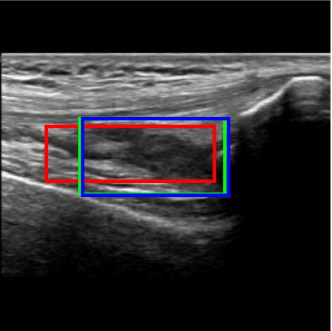

We focus on one of the three scans of the knee joint specified in HEAD-US protocol for the collection and diagnosis of joint recess distension in patients with hemophilia [7]: the SQR longitudinal scan. This scan is used to assess SQR distension and contains different characterizing elements (see Figure 1):

• The femur (blue box) usually appears as a light thick line, approximately horizontal, starting from the left side of the image and extending towards the right, often in the lower half of the image.

• The patella (red box) usually appears as a curved light line, positioned at the right border of the image, often in the top half and not entirely captured. The tendons (horizontal and parallel darker lines) can be seen on its left.

• The SQR (green box) often contains at least a small quantity of liquid and hence it is dark. In some cases, the joint recess membrane can be visible in grey. The joint recess is positioned between the femur and the patella. Its size and shape vary depending on many factors including whether it is distended or not, as explained below.

Refer to caption

(a) Example of SQR longitudinal scan

Figure 1: Image acquisition

Considering the detection problem, Figure 10 shows US images where the two approaches detected the SQR with the lowest and the highest IoU. In Figure 10a, the Multi-task approach wrongly detects as SQR an image region that is similar to an actual SQR in terms of position and shape, resulting in a very low value of IoU (0.330.330.33). In this case, also the Detection approach can not reliably detect the right target precisely, and indeed it detects only a small portion of the actual SQR (IoU=0.330.330.33). Instead, in the example shown in Figure 10b the Multi-task approach accurately detects the SQR (IoU=0.950.950.95), while the Detection approach identifies the same area with a lower IoU (0.68)0.68).

Figure 10: Detection examples. Green represents the ground truth, red and blue the results of the Multi-Task approach and Detection approach, respectively.

Figure 10d shows instead the US image for which the Detection approach provided the highest IoU value (0.960.960.96). In this case the Multi-task approach identifies the right target less precisely, resulting in a IoU of 0.550.550.55.